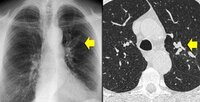

Aspergilose broncopulmonar alérgica

Tomografia computadorizada (TC) do tórax em um paciente com aspergilose broncopulmonar alérgica (ABPA): vias aéreas bronquiectásicas dilatadas impactadas por muco

Do American College of Chest Physicians, PCCU Volume 17, Lesson 17: Allergic bronchopulmonary aspergillosis; usado com permissão